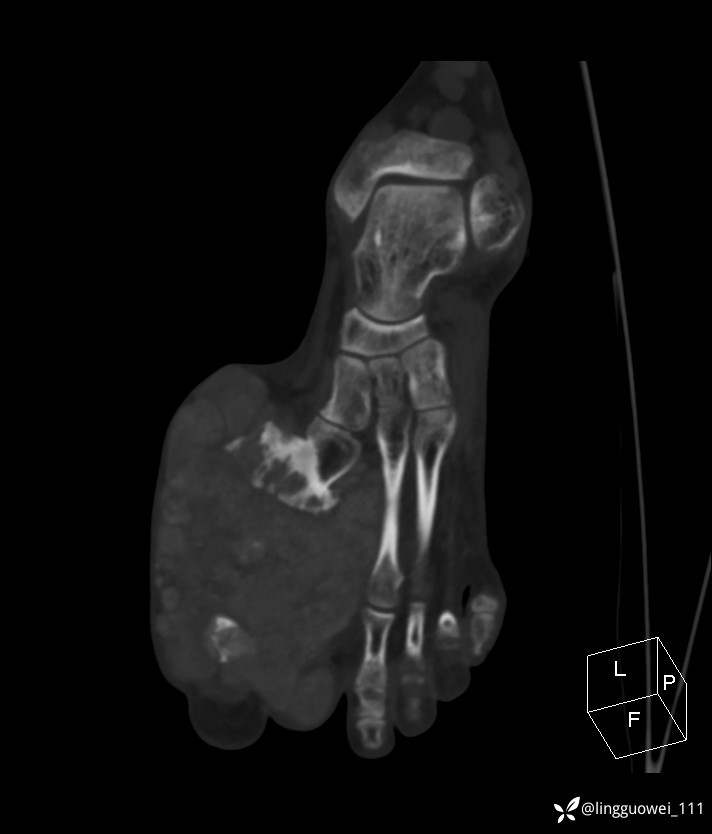

28岁男性,工作中遇到的足部最大的肿块,已补充临床资料。

28岁男性,足部肿块逐渐增大2年。能找到病因吗?

患者于2年余前高嘌呤饮食及大量饮酒后出现全身多处关节痛风石,以右足第一跖趾关节和右手为显,局部红肿热痛反复发作,自行口服药物后可缓解(药物可疑为强的松、双氯芬酸钠等,具体不详)。2年来右足痛风石明显增大,约10cm*5cm*15cm,局部红肿发热,3天前患者再次大量饮酒后痛风石顶部破溃,可见4cm*3cm皮损,较多白色豆渣样分泌物流出,为求进一步治疗来诊,门诊诊断为“右足痛风石破溃伴感染”, 收住院拟手术治疗,患者起病以来,无发热,精神佳、胃纳好、睡眠佳,大小便正常。

专科检查:右足外观畸形,足背部可见巨大痛风石形成,痛风石大小约10cm*5cm*15cm,局部皮肤红肿发热,痛风石顶部破溃,可见4cm*3cm皮损及白色豆渣样分泌物流出;痛风石界限清,质偏硬,局部触及波动感,无压痛,移动度差。右足踇趾及第2趾被痛风石压迫,关节活动受限。肢端血运、感觉无异常。 右手稍肿胀,2-5指背侧可见多发痛风石形成,最大者约花生米大小,皮肤完整未破溃,痛风石界限清,质偏硬,局部触及波动感,无压痛,移动度差。